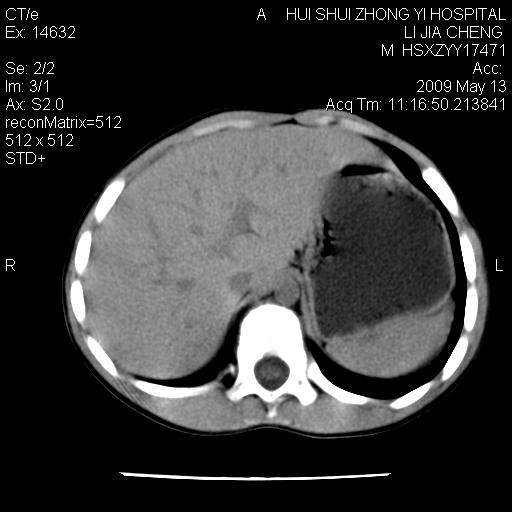

标题: PED1887:男性,6岁。反复脐周疼痛2年余。请各位老师看下腹 [打印本页]

标题: PED1887:男性,6岁。反复脐周疼痛2年余。请各位老师看下腹

该患者可自行好转,大小便未见异常,化验:便未见虫卵,血常规:wbc:8000;淋巴3600,中性45%

脂肪肉瘤可能性大,大血管边界不清,特别是腔静脉。不除外其他腹膜后肿瘤。

是不是有蛔虫哦,楼主图示块影前方肠管壁显著增厚,不除外慢性肠炎或肠壁占位,建议肠道准备后复查

肠管管壁均匀增厚,炎性可能

是小肠,壁稍厚可能是肠腔未很好充盈所致,腹部ct扫描未见明显异常。